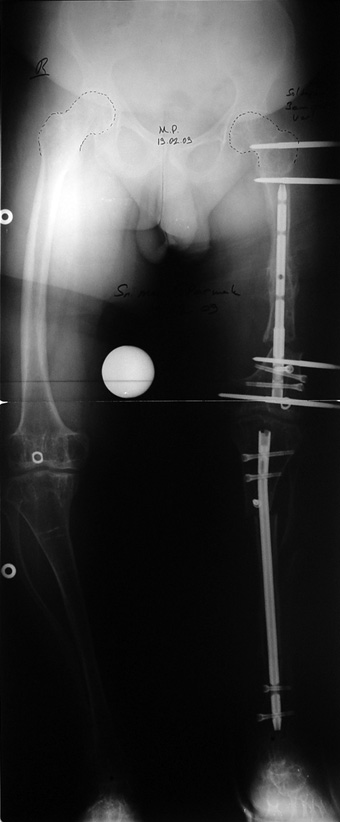

Vaka 2